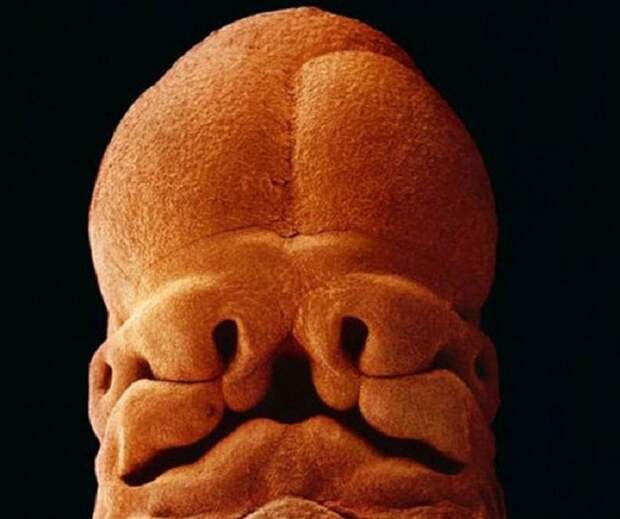

Он прекрасно чувствует себя в околоплодной среде. Пять недель и перед вами будущее лицо младенца, явно видны места. где будут располагаться рот, ноздри, глаза.  В конце восьмой недели будущий малыш немного смахивает на милого инопланетянина.

В конце восьмой недели будущий малыш немного смахивает на милого инопланетянина.  В 16 недель маленький эмбрион уже пытается исследовать окружающее его пространство при помощи рук.